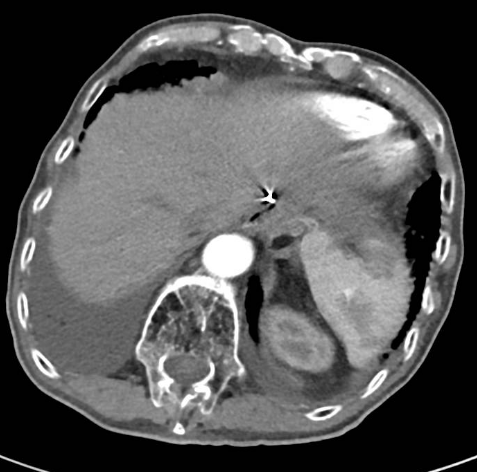

强化CT:1、符合胃部分切除术后,吻合口壁增厚伴食管下段扩张;2、胆囊结石:胆总管结合;3、肠淤张;4、前列腺增大;5、动脉硬化。

PET-CT检查:1、胃癌大部切除术后改变;肝左外叶近包膜下高代谢结节(于临近胃食管吻合口分界欠清),考虑肝转移。2、右肺中上叶多发结节伴代谢轻度增高;双肺间质纤维化;双肺泡性气肿;经根部气管憩室;贫血;动脉硬化;双侧胸膜增厚;右肺门及纵隔内多发淋巴结增生。

△ 2019.7影像学检查

2020-01-08复查腹部CT:与患者前片(2019-7-8)比较显示:食管胃吻合口区低密度病变范围较前缩小。所示腹部其余病变较前未见明显变化,双肺片状高密度影,双侧胸腔积液。

△2020.01腹部CT